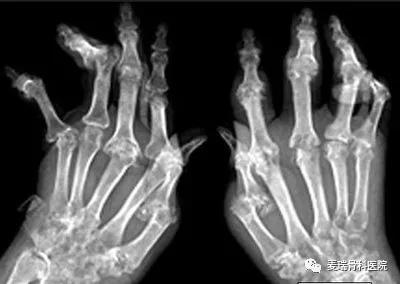

到了2011年秋天,天气转凉,她的类风湿加重了,开始出现浑身疲乏无力、胃口不好、低热跟手指麻木等症状。繁重的家务和拮据的家庭条件让她还是未引起重视,期间在马路上看到一个摆地摊的,声称“三副药15天就可以祛除关节痛疼”。她花了钱试试买了点,结果症状反而加重了,稍微活动后手指关节开始红肿,一遇到冷水就容易发白、发紫、麻木和疼痛。

由于治疗不及时,病情发展至肘关节、膝关节和脚,全身疼痛、关节僵硬,使用多种方子和产品效果都不明显。期间去了很多医院治疗,吃了很多药,也接受了很多中医调理,效果依然不明显。

桂主任经过详细检查,对她采用了医院独家研发的“针氧汉方定位治疗”疗法。这种疗法治疗类风湿标本兼治,多管齐下。既可以止痛镇痛、消散关节肿胀,治疗类风湿表层的炎症,其中的先进的PRP技术运用人体自身的免疫因子,修复受损滑膜,抗炎抗感染,从根源上促进骨的愈合,提高机体免疫力,防止复发。